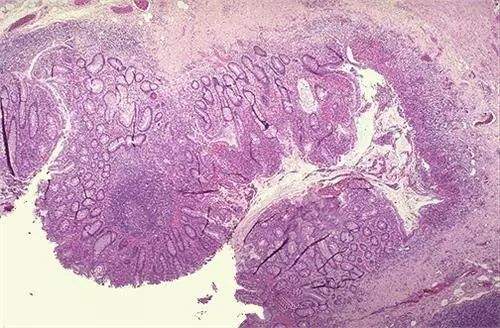

潰瘍性結(jié)腸炎(Ulcerative Colitis)是一種慢性腸道炎癥性疾病,主要影響結(jié)腸的黏膜,其癥狀包括腹瀉、腹痛、便血等,嚴(yán)重影響了患者的生活質(zhì)量,關(guān)于潰瘍性結(jié)腸炎能否治愈的問(wèn)題,一直是患者們關(guān)注的焦點(diǎn),本文將就此問(wèn)題展開(kāi)深度解析,并探討相關(guān)的應(yīng)對(duì)策略。

潰瘍性結(jié)腸炎是一種腸道炎癥,其確切原因尚不完全清楚,可能與遺傳、環(huán)境、免疫等因素有關(guān),病變主要限于大腸黏膜與黏膜下層,常見(jiàn)癥狀包括血性腹瀉、腹痛、體重減輕等,該疾病呈慢性經(jīng)過(guò),常有反復(fù)發(fā)作,但并非不可治療。